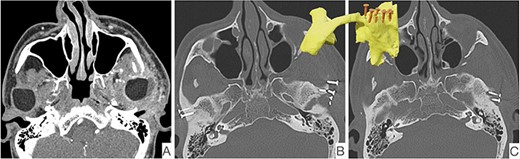

This report is about a 63-year-old patient suffering of bilateral deforming TMJ arthrosis (Wilkes-V) from a bilateral condylar fracture. In 2019 he presented himself to the Department of Oral and Maxillofacial Surgery, showing painful palpation above both TMJs and a severely decreased mouth opening (maximum interincisal distance of 1.5 cm). A computed tomography (CT) scan then revealed pathognomonic changes with flattening of the condyle and articular eminentia as well as partial ankylosis of the right TMJ (Fig. 1). Based on these findings, we decided for a bilateral TMJ-TJR. At this point, the patient only wanted one side replaced for the time being. After impressions were taken, plaster models were 3D-surface scanned and in combination with the CT dataset further processed by Zimmer-BiometTM (Warsaw, USA) for patient-specific TJR (PSI-TJR) fabrication. Another 3 months later, the TMJ-TJR of the right side could be carried out (Fig. 2). Postoperatively the patient received antibiotics for overall 7 days. Satisfied with the result, the patient requested reconstruction of the left TMJ 6 months later. With an improved mouth opening (2.8 cm), impressions were taken using an intraoral scanner. After PSI fabrication, the operation was carried out 9 months after (Fig. 3). Six weeks following surgery, the patient presented with a painful preauricular swelling on the left side, which was diagnosed as aseptic inflammation in the absence of erythema and pathologic joint puncture. Showing a periarticular edema, a broken screw and radial osteolysis around the drilling channels, a subsequent CT scan indicated the loosening of the ultra-high-molecular-weight-polyethylene (UHMWPE) fossa component (Fig. 4). In view of the long production time of new custom-made components and the damaged implant site, we decided to explant the fossa and to temporarily replace it with a non-fixed patient-specific spacer made of COPAL®-bone-cement (Fig. 5) (gentamicin and clindamycin additive) (Haereus; Hanau, Germany). The workflow included the surface scan of the original fossa-drilling template, the computer-aided design of a two-part press mould and the intraoperative fossa fabrication from COPAL®-bone-cement. With the use of a rubber elastic intermaxillary fixation, the vertical mandibular relation could be secured, painful movements and muscle shortening avoided and the risk of perioperative infection could be sufficiently minimized (Fig. 6). After 3 months without complications, the patient-specific COPAL® component could be removed and the new patient-specific UHMWPE fossa inserted within sufficiently regenerated bone (Fig. 7).

CT in coronal view with pathognomonic picture of deforming temporomandibular joint arthrosis on both sides.